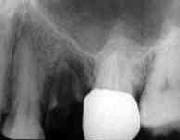

初診時所見:

│5根尖部には根尖病巣が認められ、歯肉縁下に及ぶカリエスは残存歯質の半分以上に およぶものの骨植は堅固であった。

処置および経過:

│5の根管治療終了後、通法に従いコアーおよび最終補綴物を装着し治療を終了。 5年後に補綴物を再製したものの、1年前に脱落するまでの15年間経過良好。